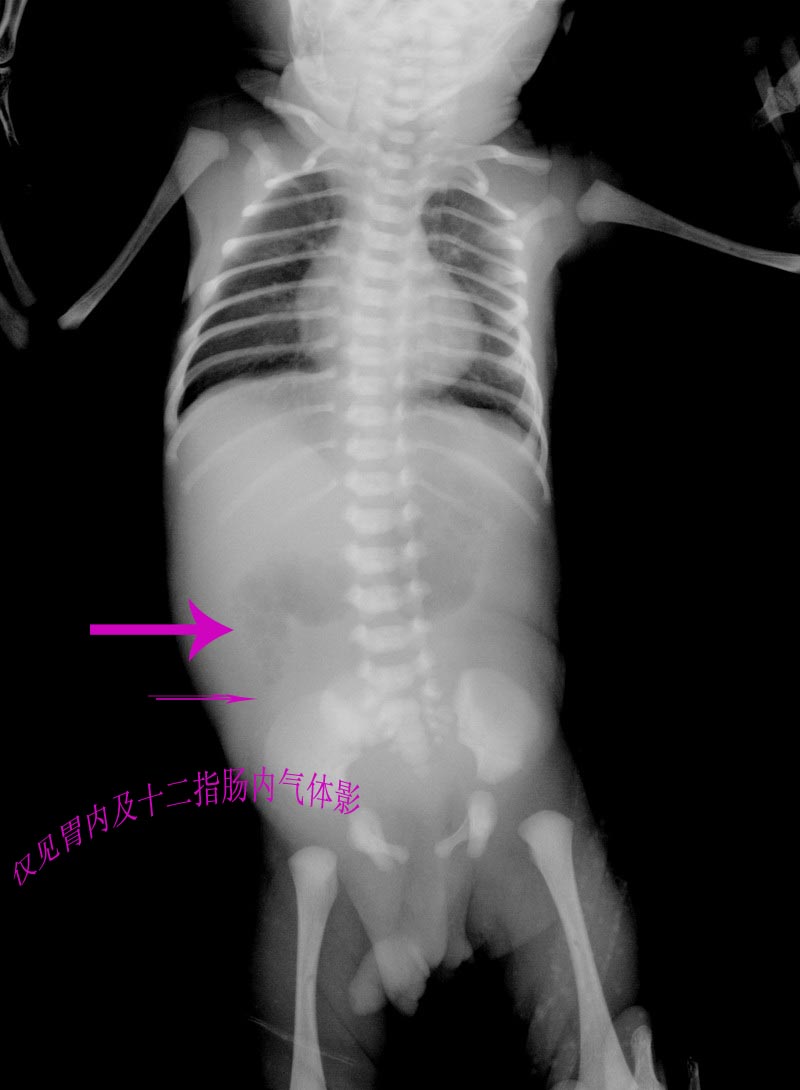

以下是引用黑白光影在2009-3-30 22:21:00的发言:[br]来到这个也间才一小时,如有症状考虑先天性十二指肠球后闭锁或环形胰腺可能。

以下是引用黑白光影在2009-3-30 22:21:00的发言:[br]来到这个也间才一小时,如有症状考虑先天性十二指肠球后闭锁或环形胰腺可能。

以下是引用jiangjing在2009-3-31 14:12:00的发言:[br]考虑先天性十二指肠球后闭锁或环形胰腺可能。

以下是引用jiangjing在2009-3-31 14:12:00的发言:[br]考虑先天性十二指肠球后闭锁或环形胰腺可能。